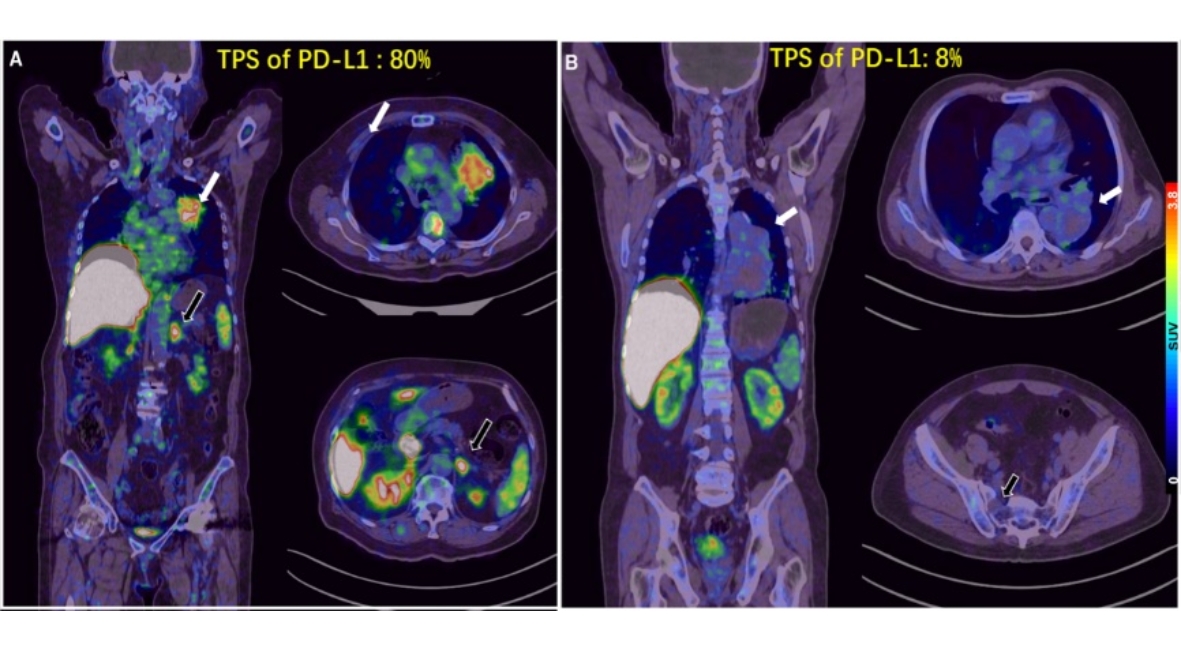

5.目前預(yù)測PD-1/PD-L1單抗療效較為成熟的生物標(biāo)志物主要是PD-L1表達(dá)。北京大學(xué)腫瘤醫(yī)院核醫(yī)學(xué)科和胸部腫瘤內(nèi)一科合作,研制Ga-68標(biāo)記的PD-L1靶向低分子量多肽(LMW)探針,首次用于進(jìn)展期肺癌的臨床轉(zhuǎn)化研究展示了在可行的時間窗內(nèi)用PET顯像的方式對患者進(jìn)行PD-L1表達(dá)水平檢測的可行性和研究潛力。相關(guān)成果以“First-in-human evaluation of a PD-L1-binding peptide radiotracer in non-small cell lung cancer patients with PET”為題,于2021年8月發(fā)表在Journal of Nuclear Medicine雜志上。

圖5: 68Ga-LMW在不同PD-L1表達(dá)水平腫瘤中的PET分析